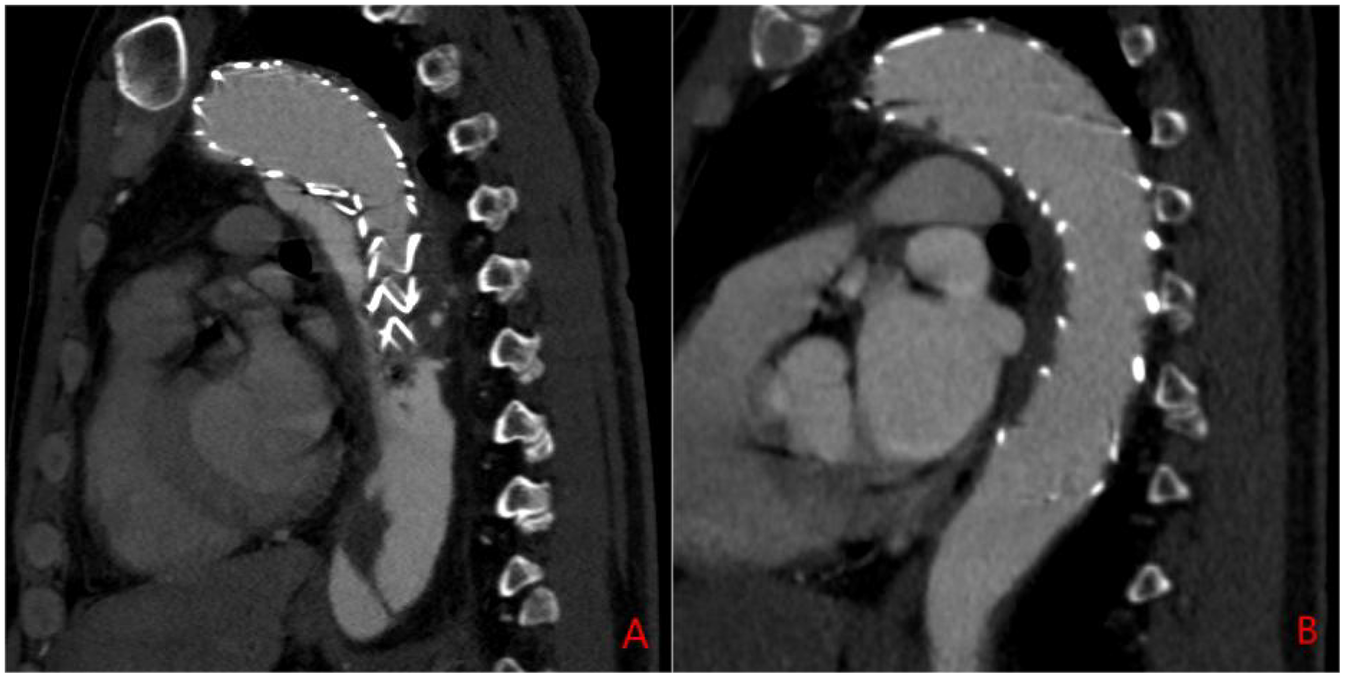

Exclusion criteria included: (1) the presence of aortic ulcers or hematomas; (2) incomplete baseline or imaging data; (3) poor-quality CTA imaging data; and (4) patients undergoing immunotherapy (e.g., chemotherapy or radiotherapy). Patients were then classified into two groups: Group 1 (residual false lumen group) and Group 2 (closed false lumen group) based on the presence or absence of a residual false lumen after TEVAR. The residual false lumen around the stent post-TEVAR is shown in Figure 1.

Figure 1

Sagittal CTA of the aorta post-TEVAR surgery. (A) Residual false lumen around the stent following TEVAR; (B) closure of the false lumen around the stent after TEVAR.